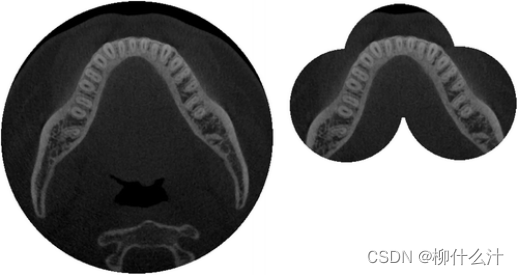

某些情况下,获得多个连续的扫描,然后将其合并为一个图像,这可以用来合并两个或更多的小的直径FOV或两个小高度FOV。在扫描之间,椅子或c型臂沿着预先设定的距离移动,在图像之间留下一个小的重叠。图像的拼接可以通过简单的重叠(因为病人在扫描之间的相对运动是确切知道的),或通过图像注册的图像自动匹配来进行

CBCT中的图像拼接,左图:覆盖整个下颌骨的大直径视场。右图:三个小直径FOV的拼接,覆盖了下颌骨的牙列。